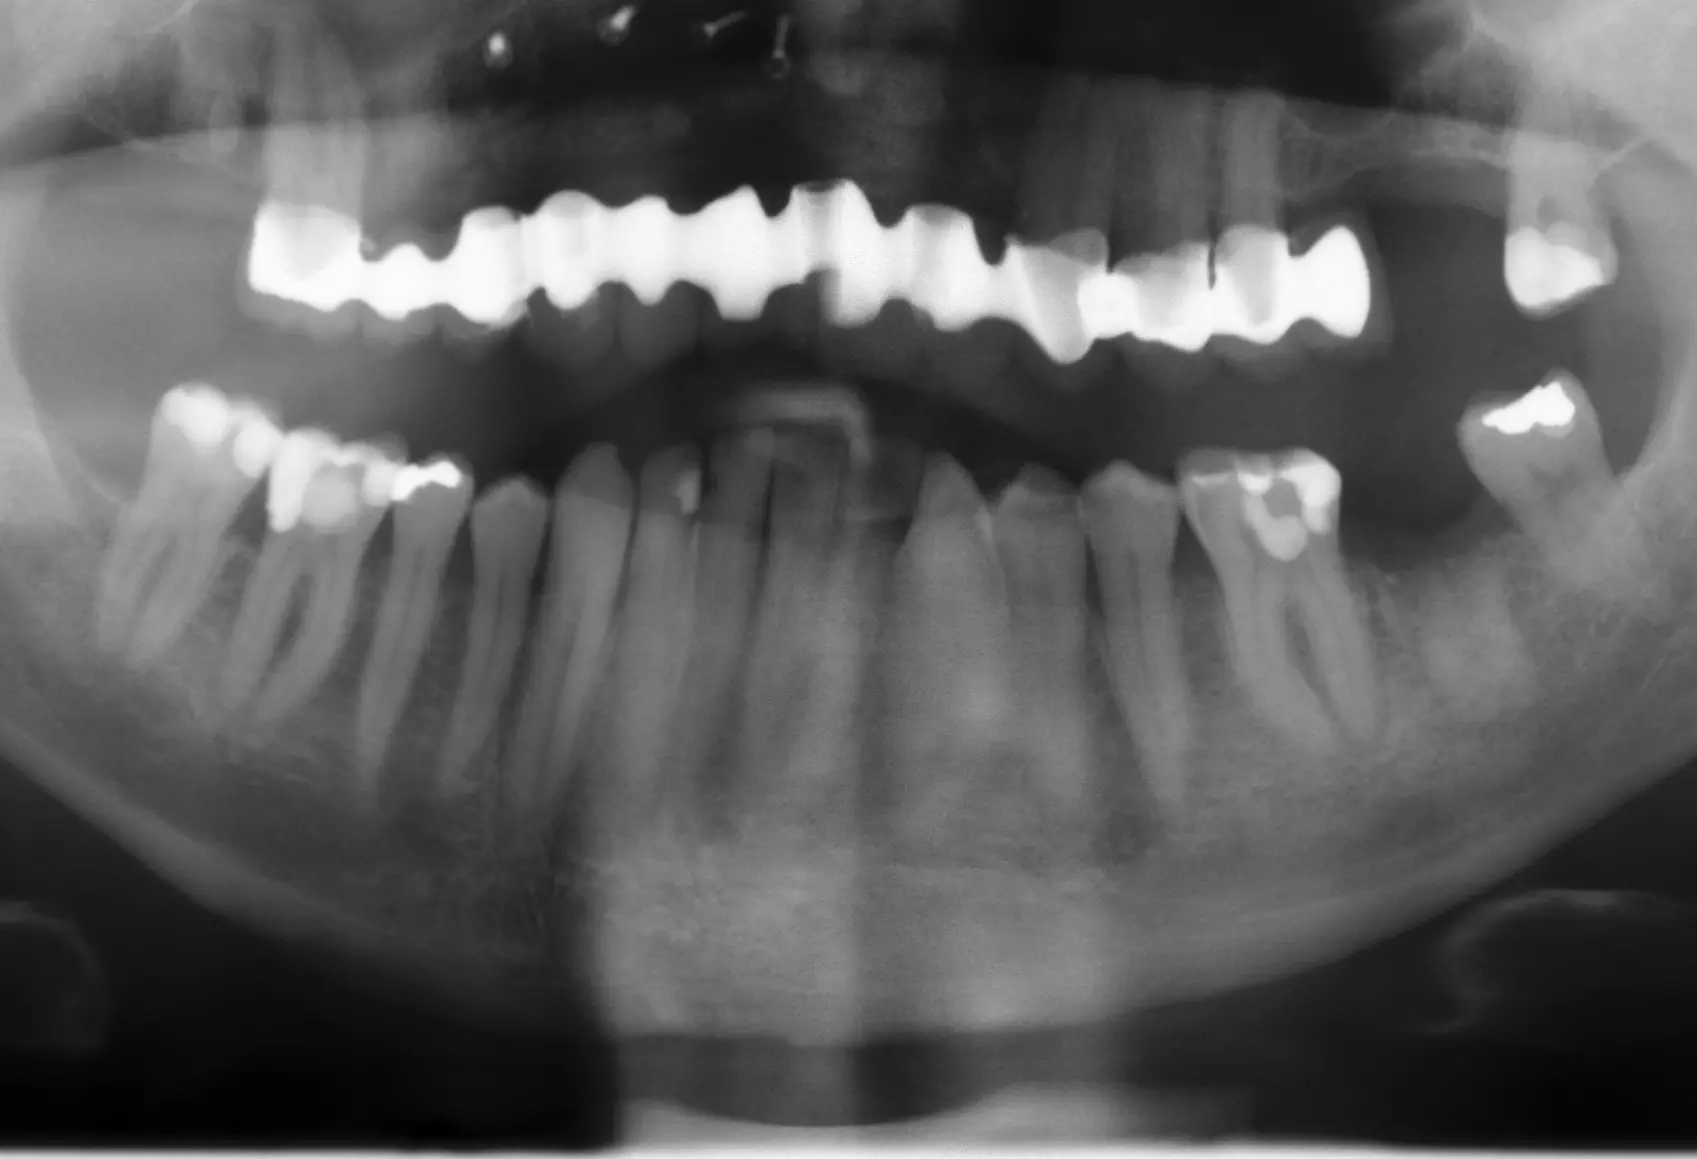

Nach sechsmonatiger Einheilzeit des Augmentats (Abb. 22 und 23) erfolgte im Januar 2019 das Re-Entry (Abb. 24). Die Mikrofixturen/Osteosyntheseschrauben wurden entfernt und vier definitive Implantate (T3, Zimmer Biomet Dental) mit einem Drehmoment von 30 Ncm nach vorherigem Gewindeschneiden (Abb. 25) inseriert: regio 015 (4,0 mm x 13 mm; simultaner direkter Sinuslift), 013 (4,0 mm x 13 mm), 021 (4,0 mm x 13 mm), 022 (3,25 mm x 13 mm). Der Knochenblock zeigte eine gute Osseointegration und Vaskularisierung, lediglich in regio 012 war er leicht gelockert, jedoch periostal gestielt (Abb. 26).

Gaps wurden mit Allograft Spongiosa aufgefüllt und mit einer resorbierbaren CopiOs Membran von 20 mm x 30 mm abgedeckt (Abb. 28). In regio 015 erfolgte ein direkter Sinuslift mit Augmentation von allogenen Knochenpartikeln (Puros Allograft Spongiosa Partikel, Zimmer Biomet Dental), gemischt mit Eigenknochen aus dem Knochenfilter. Ebenso erfolgte in regio 026, 027 ein direkter Sinuslift mit Augmentation mittels Puros Allograft Spongiosa und Eigenknochen aus dem Knochenfilter. Aufgrund der stark reduzierten crestalen Restlamelle und der Ausdehnung des Sinus (Abb. 27) wurde hier die Entscheidung zum zweizeitigen Implantationsvorgehen getroffen. Abgedeckt wurde regio 026, 027 mit einer resorbierbaren Bio-Gide Compressed Membran (Geistlich Biomaterials), die mit 2 Titanpins fixiert wurde (Abb. 28).